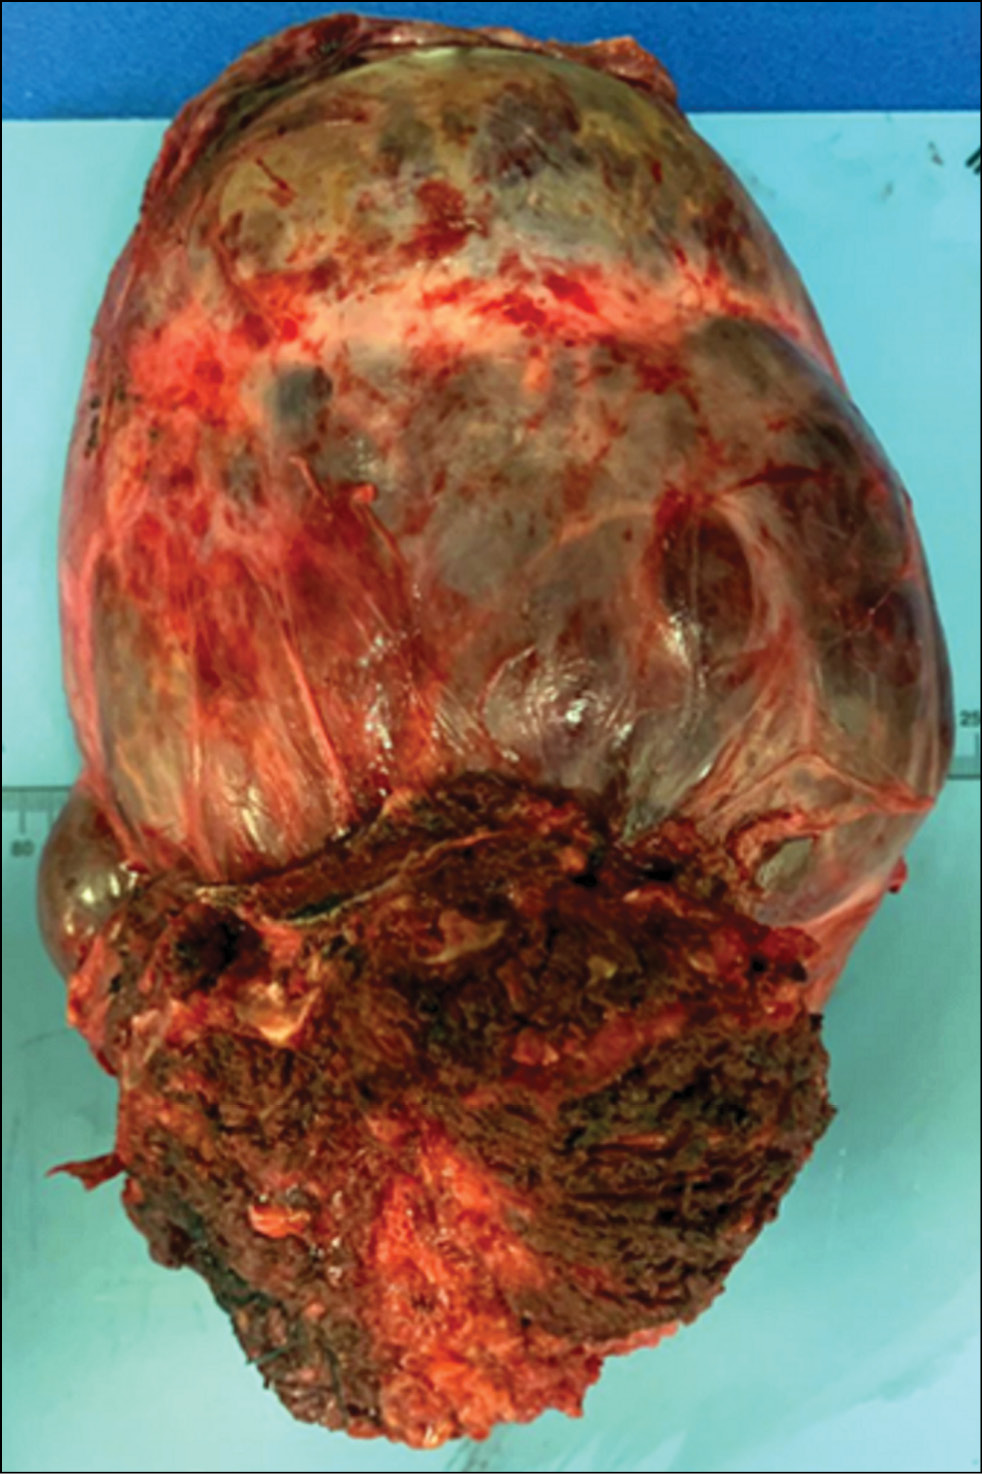

Fig. 7. Photograph of a gross specimen of a tumor removed en bloc with its covering tissues.

A tumor and a fragment of the sacrum with soft tissues measuring 20 × 11 × 10 cm were sent to the pathology department (Fig. 7). The tumor was a densely elastic lumpy nodule with a diameter of approximately 12.5 cm and was covered by a thin translucent capsule. Its content was red-blue and translucent. Along the edge, areas of bone density with several red dense fibers measuring 7.0 × 9.0 cm were defined. The node section presented multiple cystic cavities of varying sizes. Within these cavities, a dense mass with a lobular-grained appearance and a yellowish–pink liquid content (approximately 200 mL in volume) was observed. The surrounding soft tissue had varying textures, with rough areas of red–gray and yellowish–brown color. In some places, dirty yellow foci and hemorrhages injected by vessels were noted. The bone adjacent to the saw cut easily. Grayish shiny lobular soft tissue was present both inside and outside the bone during sawing (Fig. 9).